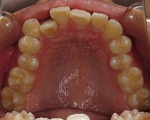

CASE2

↓前歯の歯並びを きれいに治したい。

(35歳/女性)

概要・担当医コメント:叢生・審美障害↑

動的治療期間13ヶ月(12回)/非抜歯/費用概算:55万円

上は固定式のブラケット矯正で,下は患者様ご自身が着脱するマウスピース矯正の治療を行いました.治療結果には大変満足されているそうです.